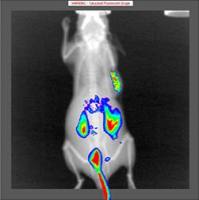

中研生物是一家专注于生物医学科研服务的新型企业,以“专注匠心科研,打造一流服务”为宗旨,致力于提供领先的、前沿的全套解决方案和技术服务,目标发展成为中国生命科学一站式服务的龙头企业。中研生物自2016年成立以来先后获得创新创业先进企业和国家高新企业等称号,现拥有1项发明专利,实用新型发明专利10项,软件著作权12项以及多项医学转化项目。总部于北京亦庄生物医药园区,并在天津、湖北和河南设立分部,向全国范围辐射,旨在为更多的生物医学研究者提供更优质的服务。中研生物拥有第三方医学检验所和多个生物资源库,现有动物实验平台、细胞生物学实验平台、分子生物学实验平台、蛋白实验平台、组织病理学实验平台、免疫学实验平台、测序研究平台等多个实验平台。并搭建了包括流式细胞仪、电镜、激光共聚焦显微镜、电位滴定(Zeta)、傅立叶红外光谱仪(FTIR)、高效液相色谱等在内的众多大型实验仪器共享平台,同时仪器设备代理品牌超过数百个。